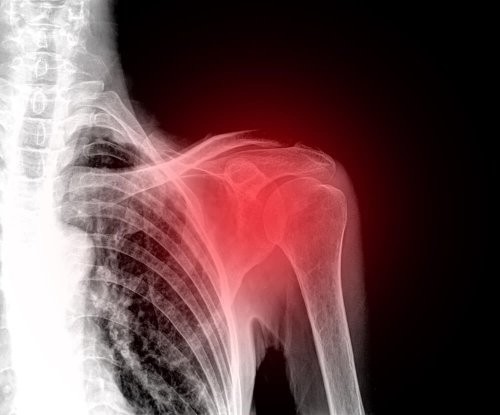

La rottura della cuffia dei rotatori è un disturbo alquanto frequente e che colpisce soprattutto le persone di mezza età. Attualmente è una delle principali cause del dolore alla spalla.

La cuffia dei rotatori è il complesso muscolo-tendineo della spalla, responsabile della stabilità e del movimento di tale articolazione. Purtroppo, la spalla è una parte del corpo particolarmente esposta a svariati problemi. Un infortunio in quest’area risulta particolarmente invalidante e doloroso. A tal proposito, nell’articolo di oggi vi diciamo di tutto quello che c’è sapere sulla rottura della cuffia dei rotatori.